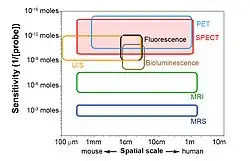

Medical imaging encompasses many different imaging modalities, which can roughly be divided into anatomical and functional imaging. Anatomical modalities (e.g. CT, MRI) mainly reveal the structure of the tissues and organs, while the functional modalities (SPECT, PET and optical imaging) mainly visualize the physiology and function of the tissue. Because none of the existing imaging modalities can provide information on all aspects of structure and function, an obvious approach is to either alter one imaging modality to the task (e.g. special imaging sequences in MRI) or to try to image a subject using multiple imaging modalities. Following the multimodality approach, in recent years the combination of a SPECT/CT system became a standard molecular imaging modality combination in both the pre-clinical and clinical fields, where the structural information of CT complements the functional information from SPECT. Nevertheless, integration of SPECT with other imaging modalities (e.g. SPECT/MR, SPECT/PET/CT[6][21]) is not uncommon.